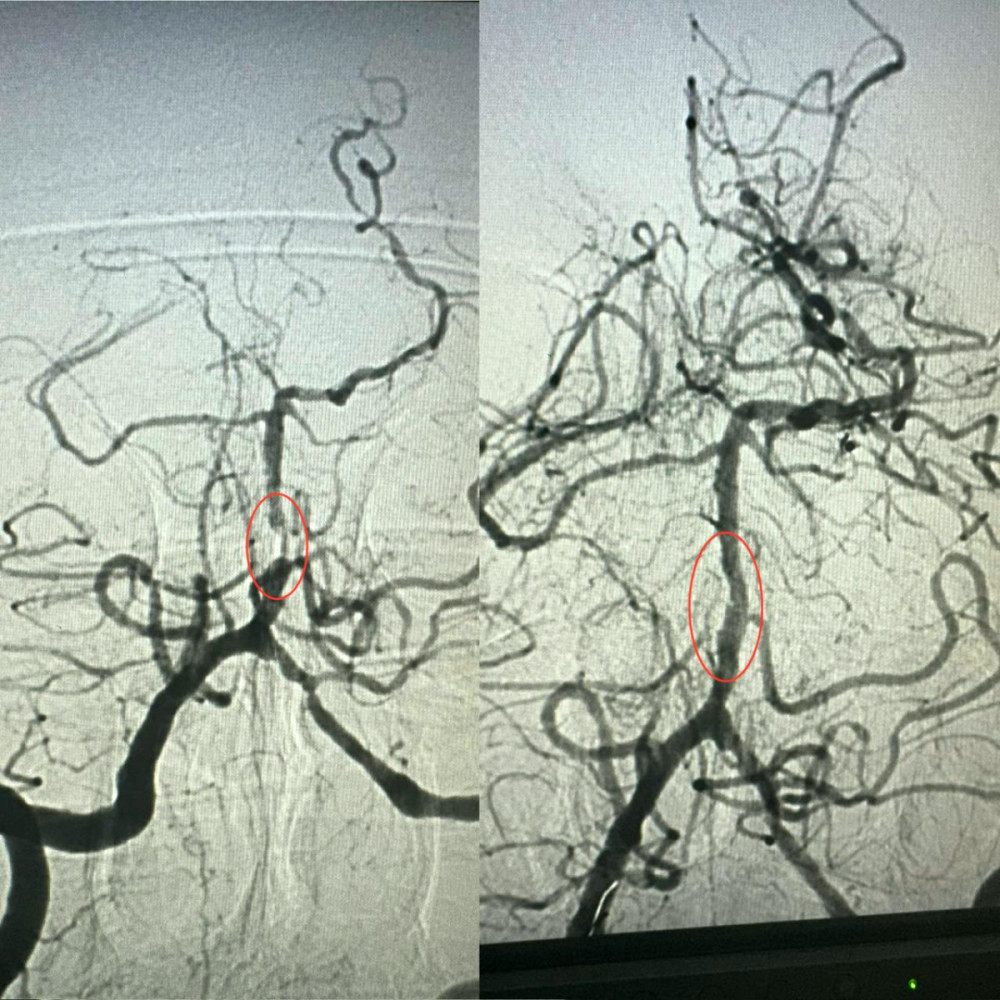

Завідувач рентгенендоваскулярного відділення Олександр Скрипка зазначив, що це був надзвичайно складний випадок - ураження стовбура мозку. Базилярна артерія була практично повністю заблокована атеросклеротичною бляшкою. Такі інсульти є одними з найнебезпечніших, і без термінової медичної допомоги шанси на виживання були б мінімальними.

Лікарі вирішили провести операцію і виконати ангіопластику артерії. Лікарня №10 має досвід використання цієї методики у кардіології для лікування атеросклерозу коронарних судин, але її застосування для мозкових судин є новаторським кроком для України.

Операція тривала близько години. Звужену артерію розширили за допомогою спеціального балона, а потім використали балон з лікарським покриттям.